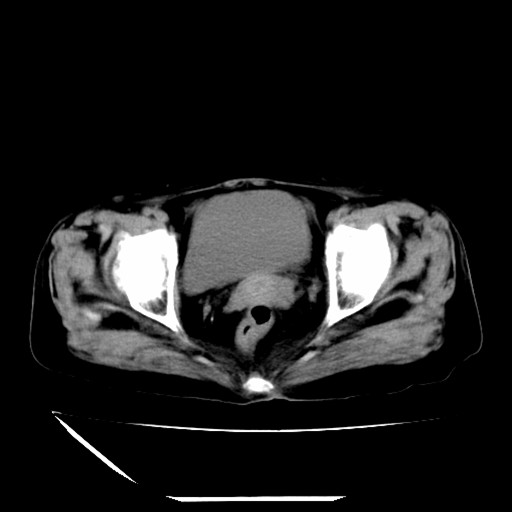

标题: CT16840:女-63岁,下腹部疼痛,

补充资料:血象是13.5,临床拟诊阑尾炎

本人诊断是右肾周围炎,阑尾炎,盆腔少许积液!

道格拉斯窝内少量积液。

支持 阑尾炎,盆腔少量积液。